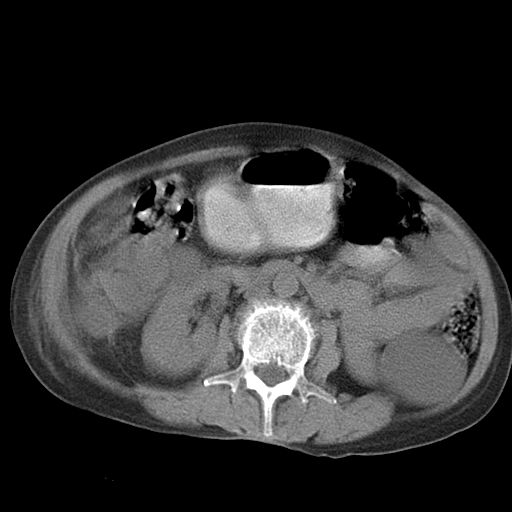

以下是引用dyqct在2006-12-7 21:08:00的发言:[br]考虑:1、肝内外胆管多发性结石伴肝左叶外侧段肝萎缩;[br] 2、右膈下多发脓肿;[br] 3、右侧少量胸腔积液、斜裂积液;[br] 4、左肾囊肿。

以下是引用jiazh在2006-12-7 20:37:00的发言:[br]肝脏周围半狐形低密度影,肝脏表面受压推移,考虑膈下脓肿可能性大;2、右侧胸腔积液

以下是引用拾荒者在2006-12-7 21:44:00的发言:[br]肝内外胆管多发结石,右膈下多发脓肿,右胸膜腔及叶间裂积液,左肾囊肿。[br] [br]